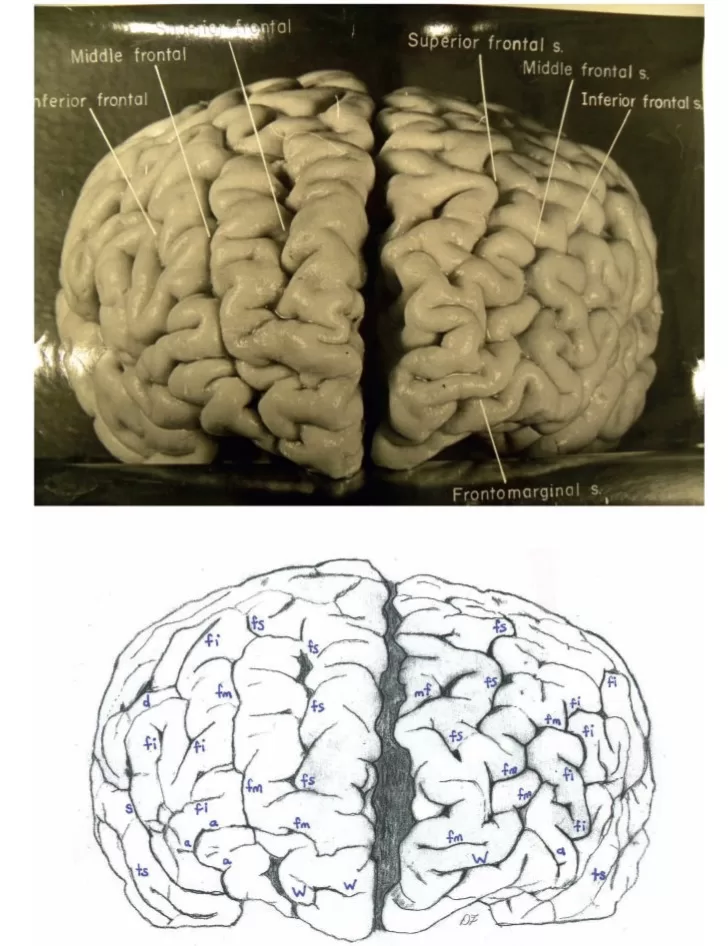

Top: Dorsal photograph of Einstein’s brain with original labels. Bottom: Our identifications. a2 = angular; a3 = anterior occipital; c = central; e = processus acuminis; fm = midfrontal; fs = superior frontal; inp = intermediate posterior parietal; ip = intraparietal; m = marginal; mf = medial frontal; ocs = superior occipital; otr = transverse occipital; par = paroccipital; pci = precentral inferior; pcs = precentral superior; pma = marginal precentral; pme = medial precentral; po = parieto-occipital; prc = paracentral; ps = superior parietal; pst = transverse parietal; pti = postcentral inferior; pts = postcentral superior; rc = retrocalcarine; u = unnamed. k = presumed motor cortex for right hand; K = ‘knob’ representing motor cortex for left hand. In both hemispheres, e limits anteriorly the first annectant gyrus, a pli de passage of Gratiolet that connects the parietal and occipital lobes, indicated by red arrows (see also Fig. 7). This figure is reproduced with permission from the National Museum of Health and Medicine.Top: Photographs of the left (L) and right (R) lateral surfaces of Einstein’s brain taken with the front of the brain rotated toward the viewer, with original labels. Bottom: Our identifications. Numbers 1–4 indicate four gyri in Einstein’s right frontal lobe, rather than three as is typical; K = ‘knob’ representing motor cortex for left hand. Submerged gyri are shaded red near the diagonal sulcus on each side. It is clear from the left hemisphere that the posterior ascending limb of the Sylvian fissure and the postcentral inferior sulcus are not confluent, contrary to the literature. Sulci: a = additional inferior frontal; a1 = ascending branch of the superior temporal sulcus; a2 = angular; aS = posterior ascending limb of the Sylvian; c = central; d = diagonal; dt = descending terminal branch of the Sylvian; fi = inferior frontal; fm = midfrontal; fs = superior frontal; ht = posterior terminal horizontal branch of the Sylvian; ip = intraparietal; mf = medial frontal; pci = precentral inferior; pcs = precentral superior; pma = marginal precentral; pti = postcentral inferior; pts = postcentral superior; R = ascending ramus of anterior Sylvian fissure; R’ = horizontal ramus of anterior Sylvian fissure; S = Sylvian fissure; sa = sulcus acousticus; sca = subcentral anterior; scp = subcentral posterior; sip = intermedius primus of Jensen; ti = inferior temporal; tri = triangular; ts = superior temporal; tt = transverse temporal; u = unnamed; W = fronto-marginal of Wernicke. 1 = superior frontal gyrus; 2 = atypical superior middle frontal gyrus; 3 = atypical inferior middle frontal gyrus; 4 = inferior frontal gyrus (usually the ‘inferior third frontal gyrus’). The figure reproduced with permission from the National Museum of Health and Medicine.Top: Photographs of the left (L) and right (R) lateral surfaces of Einstein’s brain taken from a traditional view, which lack original labels. Bottom: Our identifications. Numbers 1–4 on the right hemisphere indicate four gyri in Einstein’s right frontal lobe, rather than three as is typical. Sulci: a = additional inferior frontal; a1 = ascending branch of the superior temporal sulcus; a2 = angular; a3 = anterior occipital; aS = posterior ascending limb of the Sylvian; c = central; d = diagonal; dt = descending terminal branch of the Sylvian; e = processus acuminis; fi = inferior frontal; fm = midfrontal; fs = superior frontal; ht = posterior terminal horizontal branch of the Sylvian; inp = intermediate posterior parietal; ip = intraparietal; mf = medial frontal; ocl = lateral occipital; ocs = superior occipital; otr = transverse occipital; par = paroccipital; pci = precentral inferior; pcs = precentral superior; ps = superior parietal; pti = postcentral inferior; pts = postcentral superior; R = ascending ramus of anterior Sylvian fissure; R’ = horizontal ramus of anterior Sylvian fissure; S = Sylvian fissure; sa = sulcus acousticus; sca = subcentral anterior; scp = subcentral posterior; sip = intermedius primus of Jensen; ti = inferior temporal; tri = triangular; ts = superior temporal; tt = transverse temporal; u = unnamed. 1 = superior frontal gyrus; 2 = atypical superior middle frontal gyrus; 3 = atypical inferior middle frontal gyrus; 4 = inferior frontal gyrus (usually the ‘inferior third frontal gyrus’). K = ‘knob’ representing motor cortex for left hand. The figure is reproduced with permission from the National Museum of Health and Medicine.Top: Photographs of the left (L) and right (R) lateral surfaces of Einstein’s brain taken with the back of the brain rotated towards the viewer, with original labels. Bottom: Our identifications. The arrows indicate the pre-occipital notch at the inferolateral border of each hemisphere, which indicate the approximate inferior boundary between the lateral surfaces of the temporal and occipital lobes; on the right, an apparent artificial cut severed the rostral tip (shaded red) of a gyrus in the posterior part of the inferior temporal lobe. This cut appears to be a lateral extension of that observed on the right side of the base of the brain (Fig. 6). Typically, the supramarginal gyrus surrounds the posterior ascending limb of the Sylvian, and the angular gyrus surrounds the upturned end(s) of superior temporal sulcus. These gyri are separated approximately at the level of the intermedius primus sulcus of Jensen and together form the inferior parietal lobule. The supramarginal gyri are shaded blue; the angular gyri are aqua. In the left hemisphere, part of the cortical region above posterior terminal horizontal branch of the Sylvian is shaded an inbetween colour because it could arguably belong to either gyrus. Einstein’s inferior parietal lobules have different shapes in the two hemispheres, and appear to be relatively larger on the left side. Sulci: a1 = ascending branch of the superior temporal sulcus; a2 = angular; a3 = anterior occipital; aS = posterior ascending limb of the Sylvian; c = central; dt = descending terminal branch of the Sylvian; e = processus acuminis; ht = posterior terminal horizontal branch of the Sylvian; i = inferior polar; inp = intermediate posterior parietal; ip = intraparietal; lc = lateral calcarine; oci = inferior occipital; ocl = lateral occipital; ocs = superior occipital; otr = transverse occipital; par = paroccipital; ps = superior parietal; pti = postcentral inferior; pts = postcentral superior; rc = retrocalcarine; S = Sylvian fissure; scp = subcentral posterior; sip = intermedius primus of Jensen; ti = inferior temporal; ts = superior temporal; u = unnamed. The figure is reproduced with permission from the National Museum of Health and Medicine.Top: Photograph of a frontal view of Einstein’s brain in an unconventional orientation, with original labels. Bottom: Our identifications of sulci. a = additional inferior frontal; fi = inferior frontal; fm = midfrontal; fs = superior frontal; mf = medial frontal; S = Sylvian fissure; ts = superior temporal; W = fronto-marginal of Wernicke. The figure is reproduced with permission from the National Museum of Health and Medicine.Top: Separate photographs of the right (R) and left (L) basal views of Einstein’s bisected brain with cerebellum removed and original labels. Bottom: Our identifications. The two photographs are not to the same scale and the right hemisphere is rotated slightly laterally compared with the left, as suggested by a published basal photograph of the entire brain with its cerebellum attached (Witelson et al., 1999b). The base of Einstein’s brain appears to have been accidentally cut, perhaps with a scalpel, as indicated in red shading. This may have occurred during removal of the dura mater (tentorium cerebelli) that separates the dorsum of the cerebellum from the inferior surface of the occipital lobes. Magnifying the photographs on a computer screen should facilitate observation of these cuts. See Fig. 4 for an extension of this cut that reached the right lateral surface of the temporal lobe where it severed the tip of a gyrus (shaded in red). Sulci: arc = arcuate orbital; col = collateral; fi = inferior frontal; i = inferior polar; mo = medial orbital; oa = anterior orbital; oal = lateral anterior orbital; oci = inferior occipital; oct = occipito-temporal; op = posterior orbital; opl = lateral posterior orbital; os = olfactory; R’ = horizontal ramus of anterior Sylvian fissure; rh = rhinal; ti = inferior temporal. Abbreviations of other features: los = lateral olfactory stria; mb = mammillary body; mos = medial olfactory stria; ob = olfactory bulb; on = optic nerve; ot = olfactory tract. The figure is reproduced with permission from the National Museum of Health and Medicine.Top: Photograph of an occipital view of Einstein’s brain in an unconventional orientation, with original labels. Bottom: Our identifications. In both hemispheres, a processus acuminis limits anteriorly the first annectant gyrus, a pli de passage of Gratiolet that connects the parietal and occipital lobes, indicated by red arrows (see also Fig. 1). See Fig. 10B for shading of the superior and inferior parietal lobules and the occipital lobe on this image. Sulci: a2 = angular; a3 = anterior occipital; c = central; cu = cuneus; e = processus acuminis; inp = intermediate posterior parietal; ip = intraparietal; lc = lateral calcarine; m = marginal; oci = inferior occipital; ocl = lateral occipital; ocs = superior occipital; otr = transverse occipital; par = paroccipital; pcs = precentral superior; po = parieto-occipital; ps = superior parietal; pst = transverse parietal; pti = postcentral inferior; pts = postcentral superior; rc = retrocalcarine; sp = subparietal; ss = superior sagittal; ti = inferior temporal; ts = superior temporal. The figure is reproduced with permission from the National Museum of Health and Medicine.Top: Photographs of the left (L) and right (R) medial surfaces of Einstein’s brain with original labels. Bottom: Our identifications. Arrows indicate sulci that extend onto the dorsolateral surface of the brain. Sulci: ac = anterior calcarine; apo = anterior parolfactory; c = central; ca = callosal; cal = calcarine; ci = cingulate; cu = cuneus; li = lingual; lp = limiting sulcus of precuneus; m = marginal; mf = medial frontal; otr = transverse occipital; pc = paracalcarine; pma = marginal precentral; pme = medial precentral; po = parieto-occipital; prc = paracentral; pst = transverse parietal; rc = retrocalcarine; ri = inferior rostral; rs = superior rostral; si = inferior sagittal; sp = subparietal; ss = superior sagittal; u = unnamed. Other abbreviations: cc = corpus callosum; f = fornix; hpt = hypothalamus; ipo = parieto-occipital incisure; sep = septum pellucidum; th = thalamus. See text for discussion. The figure is reproduced with permission from the National Museum of Health and Medicine.Top: Photograph of Einstein’s right insula after removal of the opercula, with original labels. Bottom: Our identifications of sulci: aps = anterior periinsular; cis = central insular; pcis = precentral insular; pis = postcentral insular; sis = short insular; sps = superior periinsular; Other identification: ia = apex of insula. The figure is reproduced with permission from the National Museum of Health and Medicine.